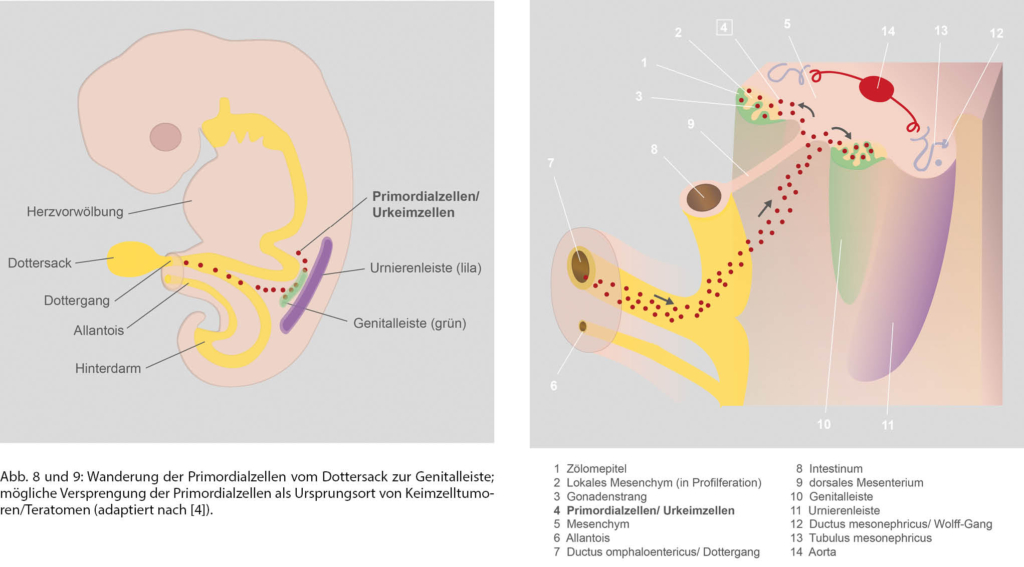

Primordialzellen (= PGC primordial germ cells, Urkeimzellen) sind die Vorläufer der Keimzellen (= Gameten, Geschlechtszellen, Spermien oder Eizellen). Unter Abfaltung des Embryos sowie chemotaktischer Reize wandern sie amöboid von der Dottersackwand über die Gastrointestinalwand und das dorsale Mesenterium zur Genitalleiste [4]. Die Genitalleisten entwickeln sich zu Keimdrüsen/Gonaden (Hoden, Ovar). Teratome entstehen in der 4.–6. Woche der Embryogenese im Mediastinum, aber auch in anderen Lokalisationen durch versprengte Primordialzellen auf ihrem Weg aus dem Dottersack (Abb. 8 und 9).